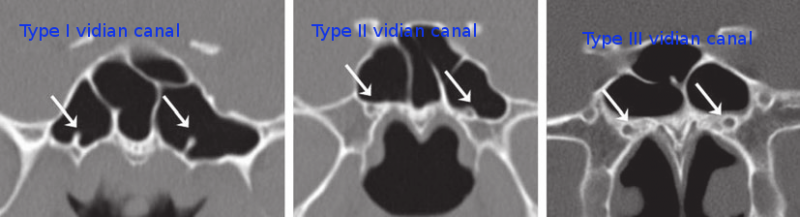

According to CT scan findings the vidian canal is classified into:

Type I:

The vidian canal lies completely within the floor of sphenoid sinus

Type II:

In this type the vidian canal partially protrudes into the floo rof sphenoid sinus

Type III:

Here the vidian canal is competely embedded in the body of sphenoid bone

Study of these anatomical differences of vidian canal in relation to thefloor of sphenoid sinus helps in deciding the surgical approach tothe nerve.